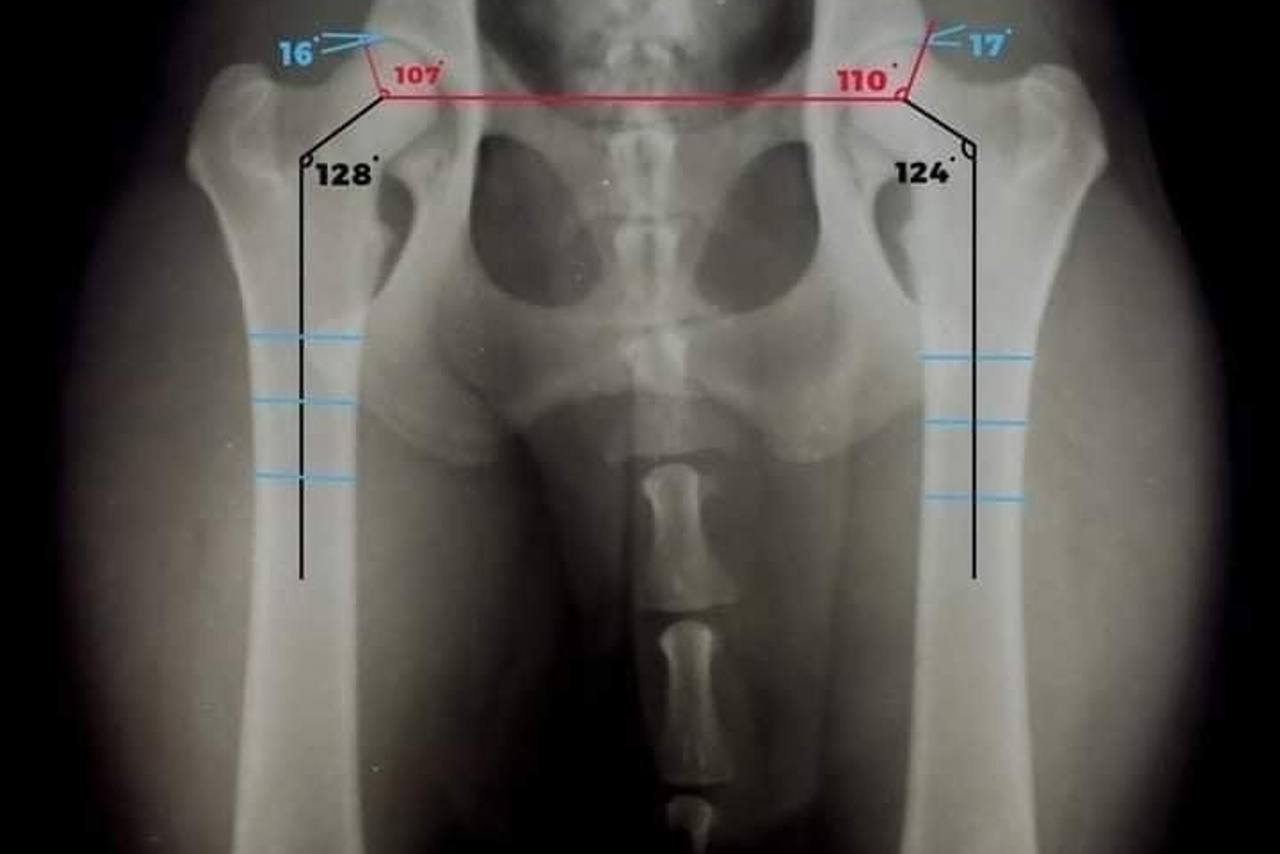

Дисплазия

Однозначного ответа наверное нет ни у кого, но я придерживаюсь мнения 80% европейских и английских...